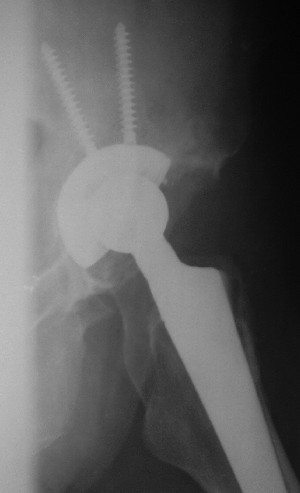

После протезирования прямой 5/04/04

|

После протезирования боковой 5/04/04

Больной 18 мая 2003 года в автоаварии получил перелом левой вертлужной впадины, вывих бедра. Госпитализирован в один из стационаров области.Вывих вправлен. В последствии бедро вывихивалось еще дважды. На консультацию был представлен снимок от 19.05.03г., больной переведен к нам 3.06.03г. Снимок при поступлении - перелом впадины, задне-верхний вывих бедра. 05.06.2003 г. выполнено открытое вправление вывиха левого бедра и остеосинтез стенки вертлужной впадины двумя винтами. Послеоперационный период без осложнений. Объем движений в левом тазобедренном суставе восстановился полностью. Выписан на амбулаторное лечение в удовлетворительном состоянии с рекомендациями 3 месяца ходить на костылях без нагрузки на оперированную конечность. На контрольных рентгенограммах левого тазобедренного сустава 13.10.2003 г. - признаки консолидации перелома; плотность, форма головки и состояние суставных поверхностей удовлетворительные. Разрешена дозированная осевая нагрузка, на конечность с использованием дополнительной опоры. 19.12.2003 г. больной обратился с жалобами на боли в левом тазобедренном суставе. На рентгенограммах левого тазобедренного сустава 19.12.2003 г., 20.02.04г. - асептичекий некроз головки бедра. 5.04.04г. - эндопротез. Сейчас ходит без трости, не хромает. Особенность эндопротезирования - при удалении винтов прослежена линия перелома заднего края впадины и предложено установить чашку несколько меньшего диаметра, чтобы она была покрыта несломанной частью.